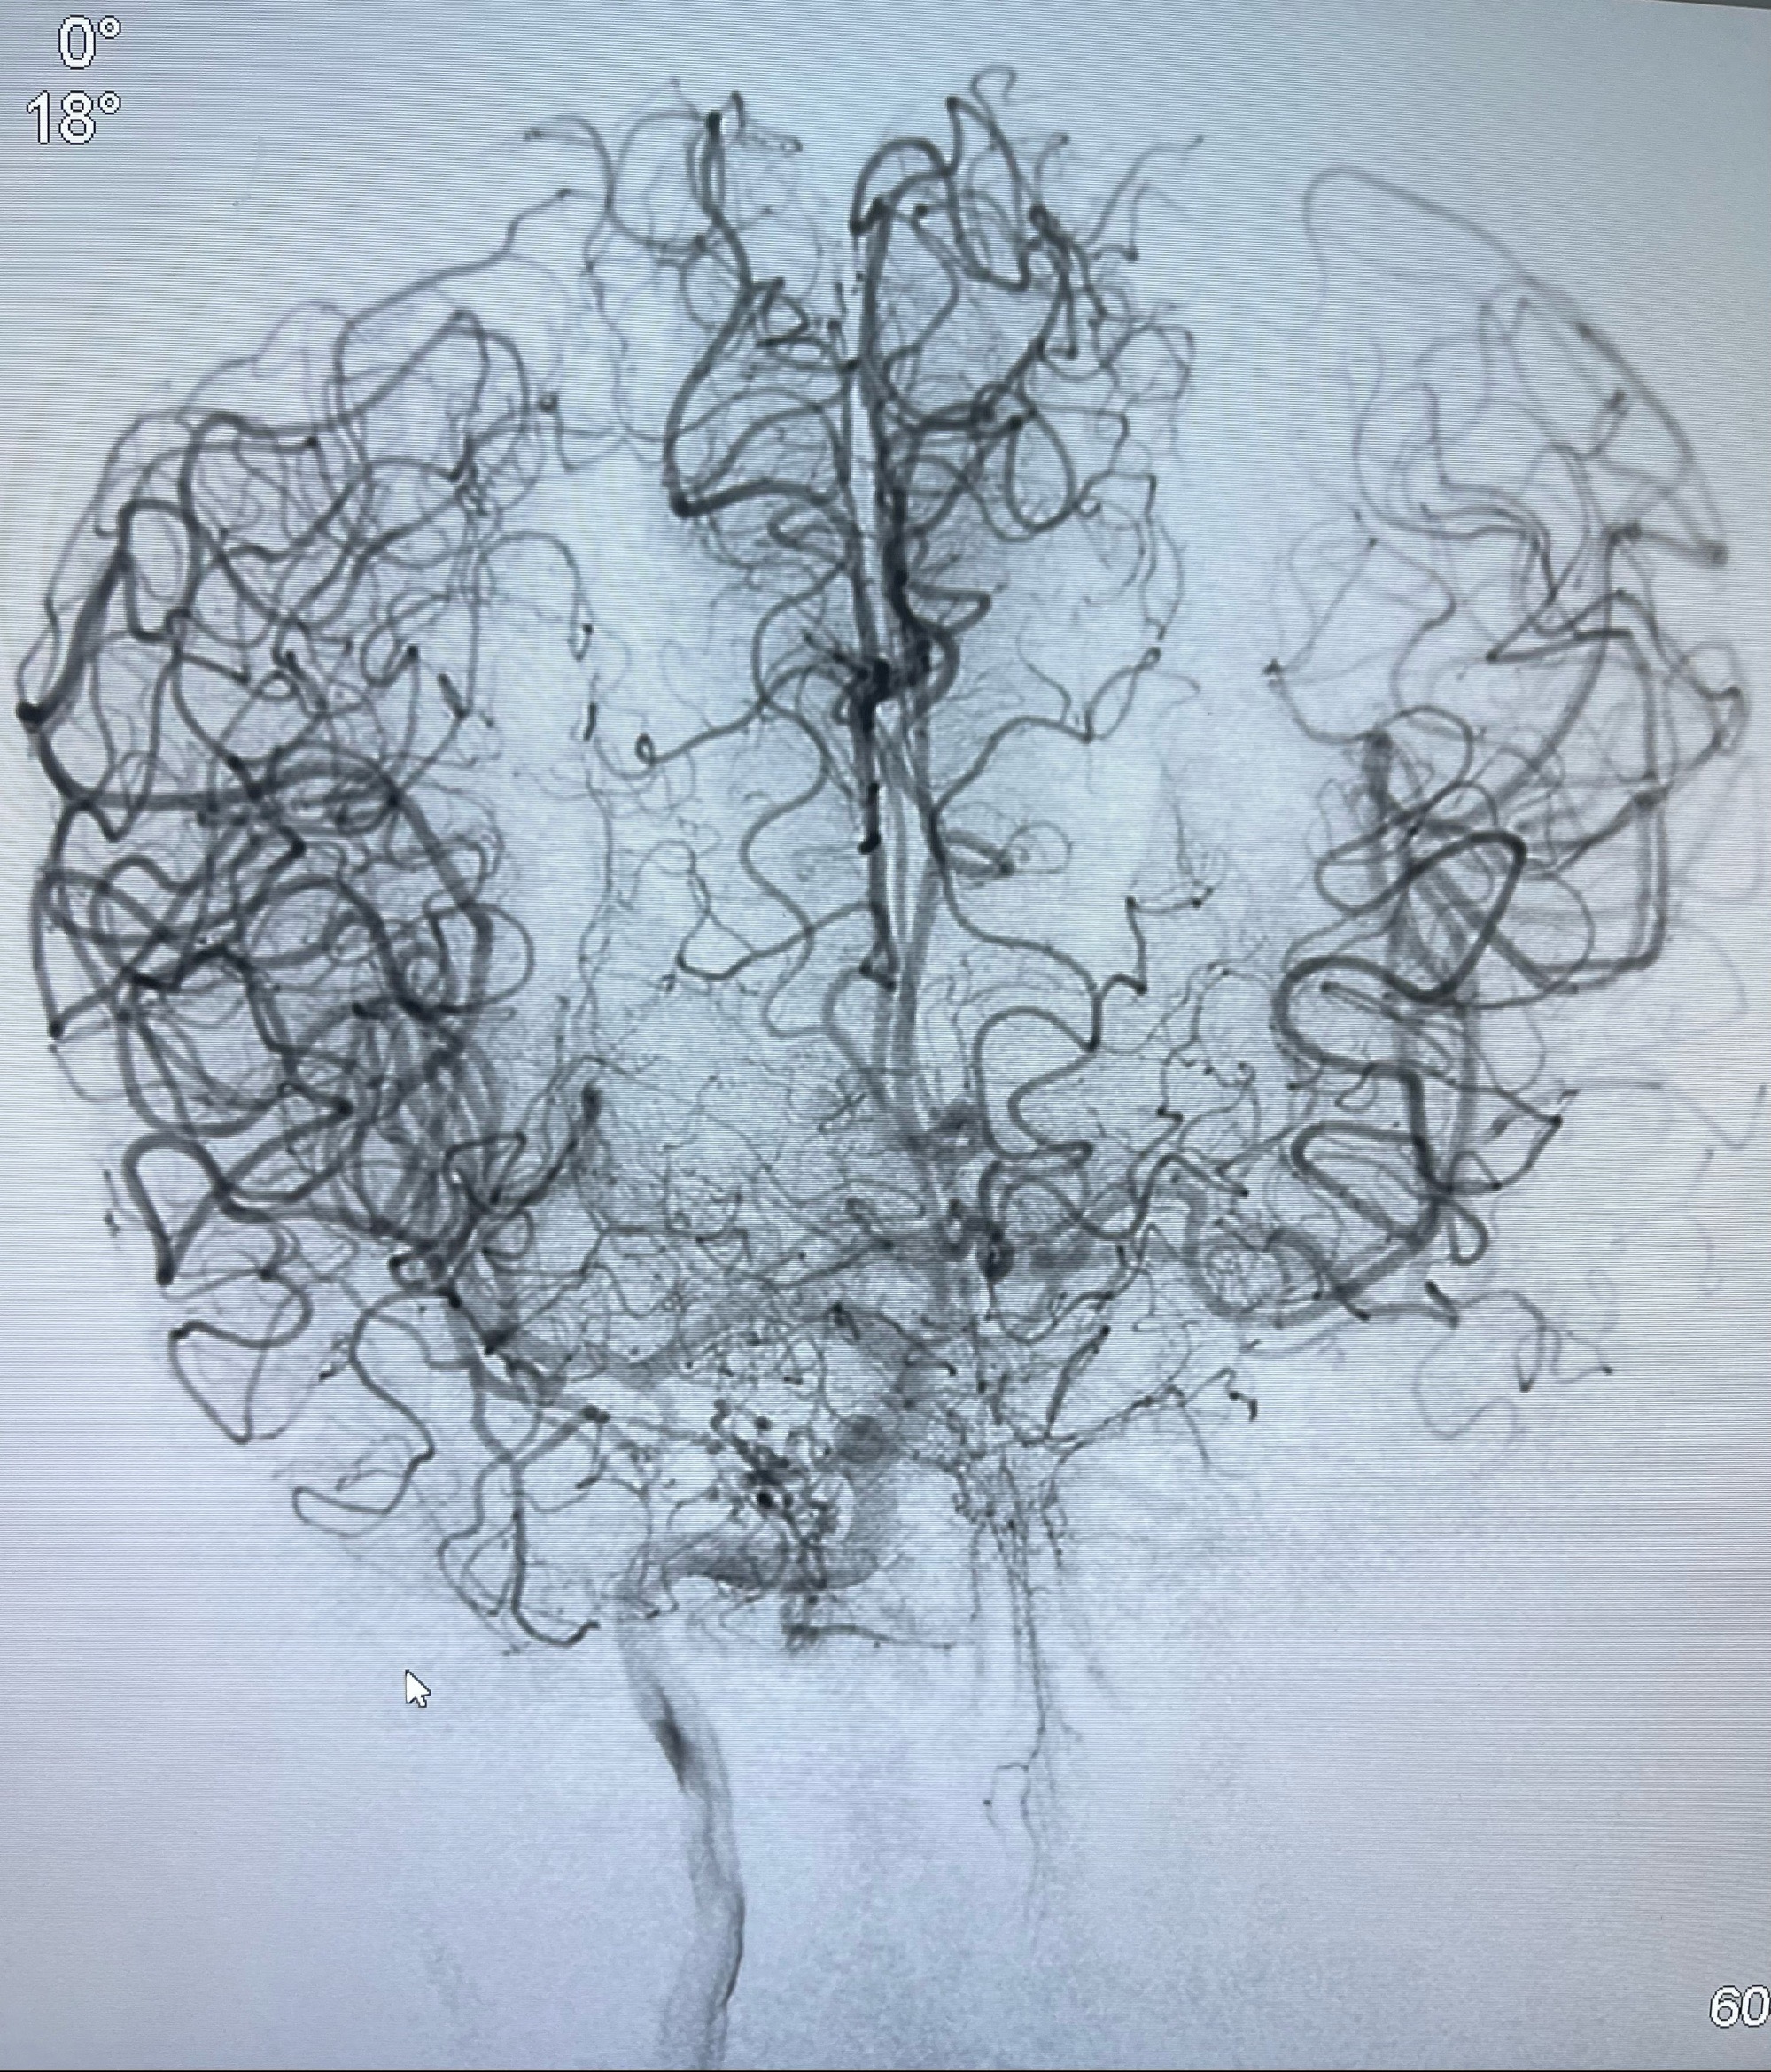

2023-07-10DSA:右侧颈内动脉岩骨段夹层伴中偏重度狭窄改变,左侧颈总动脉闭塞、右侧颈外动脉由右侧肋颈干甲颈干吻合代偿

箭头所示为颈内动脉岩骨段重度狭窄,结合MRI,考虑为肿瘤侵犯右侧颈内动脉

箭头以近至支架段管腔不规则狭窄

右侧椎动脉可见吻合代偿右侧颈外动脉

左侧颈总动脉起始段至分叉部闭塞,起始部呈现子弹头样改变

左侧椎动脉可见代偿显示左侧前循环